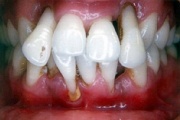

GAgP 25 aastasel suitsetaval patsiendil

GAgP 25 aastasel suitsetaval puuduliku suuhügieeniga patsiendil

GAgP kahjustused 19 aastasel patsiendil